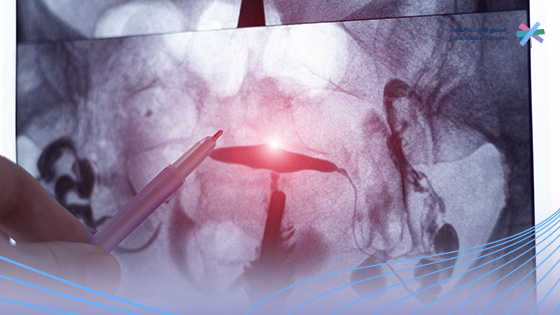

شكل أشعة الصبغة على الرحم بالصور

عند إجراء أشعة الصبغة على الرحم بالصور، يتم التقاط الصور بواسطة جهاز الأشعة بعد حقن الصبغة داخل تجويف الرحم وقنوات فالوب، وأشعة الصبغة على الرحم بالصور تظهر تفاصيل دقيقة تساعد الطبيب على تقييم صحة الجهاز التناسلي.

كيف يظهر شكل أشعة الصبغة على الرحم بالصور؟

• أشعة الصبغة على الرحم بالصور تظهر الرحم الطبيعي بشكل واضح ومنتظم، مع امتلاء تجويفه بالصبغة بشكل متساوٍ.

• الأنابيب السليمة في أشعة الصبغة على الرحم بالصور تبدو مفتوحة ويظهر مرور الصبغة خلالها حتى تتسرب إلى تجويف البطن.

• الانسداد الجزئي أو الكلي، في أشعة الصبغة على الرحم بالصور يظهر توقف الصبغة في نقطة معينة داخل الأنبوب، مما يدل على وجود مشكلة.

• الالتصاقات أو التشوهات، تظهر أيضًا في أشعة الصبغة على الرحم بالصور، وقد يظهر الرحم بشكل غير طبيعي أو غير منتظم.

أهمية شكل أشعة الصبغة على الرحم بالصور

• تساعد على تحديد سبب تأخر الحمل بدقة.

• تكشف عن أي عيوب خلقية أو مشاكل مكتسبة في الرحم.

• تمكن الطبيب من وضع خطة علاجية مناسبة، سواء دوائية أو جراحية.